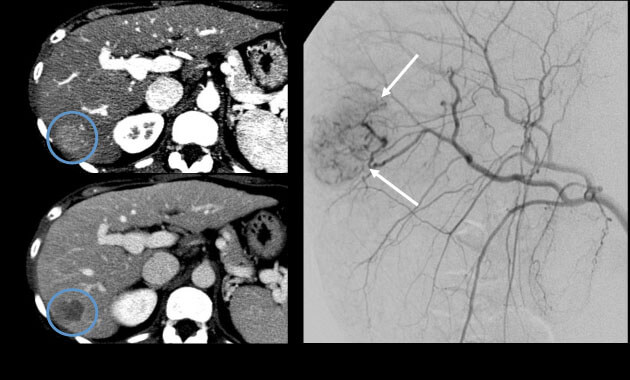

Interventional Oncology

- Conditions: Liver cancer (hepatocellular carcinoma, cholangiocarcinoma), liver metastases (colon or rectum, neuroendocrine, breast, other), kidney cancer, lung cancer, adrenal tumors

- Services: Embolization, chemoembolization, Yttrium-90 (90Y) radioembolization, microwave ablation, cryoablation, alcohol ablation, biopsies